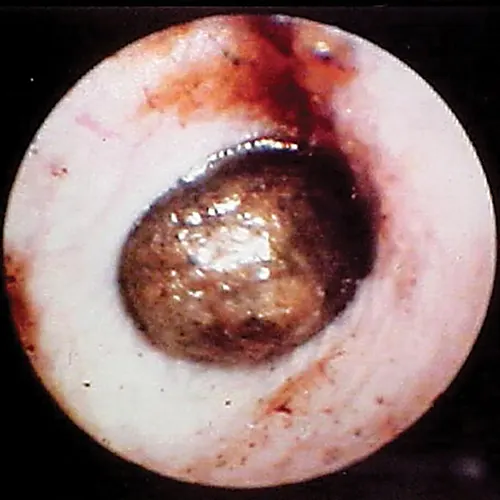

Damage to the tympanic membrane caused by trauma (eg, chewing activity of ear mites, previously ruptured eardrum that has healed) or chronic infection disturbs this epithelial migration process. When epithelial migration is slowed, as with age or from disease, debris, cerumen, and hairs accumulate on the eardrum. A ceruminolith may develop on the eardrum on the external ear canal side (Figure 14). These plugs may also consist of dried mucus or medication that has hardened in the horizontal canal.

Globoid brown-to-black mass occluding internal ear canal.

FIGURE 14

Wax plug (ceruminolith) on the eardrum

Wax plug in an ear. Accumulations of wax (cerumenolith) commonly  show up at the eardrum when the eardrum epithelial surface has been previously compromised.  Dried oily medication and inspissated mucus from the bulla can look similar.

Cerumen accumulation against the eardrum, in addition to stenosis and hyperplasia, can impede conduction of sound waves and result in temporary hearing loss. Ceruminoliths require mechanic removal, preferably with endoscopic grasping forceps through a video otoscope with the patient anesthetized. If the eardrum is not intact, exudates such as mucus and pus can leak into the horizontal canal and inspissate at the eardrum. This condition can look like a ceruminolith. The mucoid secretions dissolve in water and can be removed with a water or saline flush of the horizontal canal.